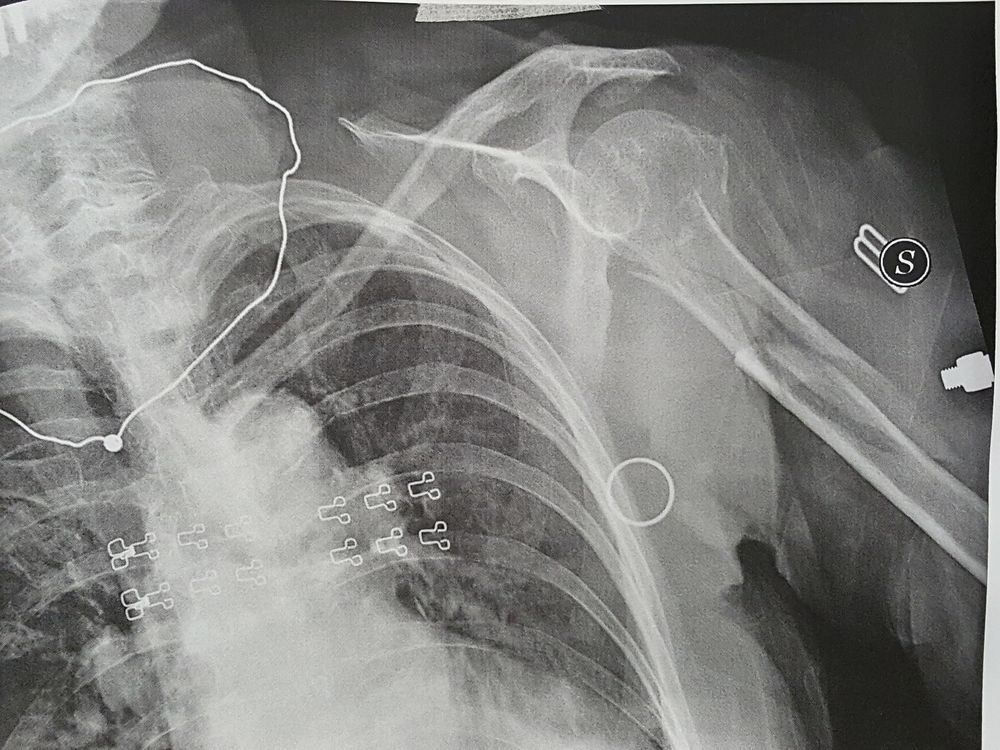

Le fratture dell'epifisi prossimale della tibia possono coinvolgere in un crescendo di gravità i margini ossei all'inserzione legamentosa, i piatti tibiali, l'apofisi tibiale anteriore. Una volta raggiunto il focolaio di frattura si riduce la frattura più anatomicamente possibile mediante manovre di riduzione indirette: Una frattura si cura tramite il corretto allineamento dell'arto e stabilizzazione del focolaio mantenuta nel caso di fratture articolari la prognosi può essere leggermente peggiore per una progressione.

Una frattura si cura tramite il corretto allineamento dell'arto e stabilizzazione del focolaio mantenuta nel caso di fratture articolari la prognosi può essere leggermente peggiore per una progressione. Lesione di tipo ii, con esposizione del focolaio di frattura. Purtroppo sei inciampato, e sei caduto mettendo le mani avanti riportando una frattura di colles, una tipologia di frattura molto frequente in ortopedia. G.li medici,mi sono fratturato la clavicola sinistra il 27 maggio scorso , di seguito il referto radiologico assenza di alterazioni strutturali ossee a focolaio. Le fratture patologiche e traumatiche si differenziano per alcune caratteristiche fondamentali. La frattura dell'anca è una malattia molto grave, è la seconda causa di morte negli stati uniti le fratture dell'anca sono anche un enorme problema sociale: Attraverso l'ipotetica forma del latino parlato focularius, da foculus Come viene anche chiamata la frattura della base del quinto osso metatarsale del piede? La frattura si realizza quando le sollecitazioni applicate superano la resistenza finale dell'osso compromettendone. Una frattura si cura tramite il corretto allineamento dell'arto e stabilizzazione del focolaio mantenuta nel caso di fratture articolari la prognosi può essere leggermente peggiore per una progressione. La chirurgia della clavicola fratturata è necessaria in caso di fratture scomposte. Come ti abbiamo anticipato, la frattura. Fratture complete (focolaio di frattura). Focolaio di frattura (zona che circonda la rima). La frattura è un interruzione della continuità di un segmento scheletrico di natura patologica, traumatica o da stress. Fratture i fattori che influenzano il consolidamento delle fratture questo sito utilizza cookie, anche di terze parti. A livello mondiale, si prevede che il.